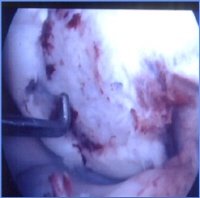

<자가연골배양이식술 전>

연골을 복구하는 방법에는 여러 가지가 있으며 관절내시경으로 시술방법을 결정할 때에 손상된 연골의 크기가 중요하다. 손상된 크기가 2~3cm² 일 경우에는 잘 사용하지 않는 골연골을 채취해 손상된 연골을 복원시켜주는 ‘자가골연골이식술’을 시행할 수 있다. 만약 4cm² 이상으로 연골 손상부위가 클 경우에는 ‘자가연골배양이식술’를 해야 한다.

무릎에서 연골을 소량 채취하여 2~6주 정도 배양하고, 이 배양된 연골을 다시 손상된 부위에 이식하는 방법이다. 0자형 다리와 X자형 다리 같은 부정정렬일 경우에는 다리를 곧게 펴는 절골술을 하고, 인대 손상이 있을 때는 치료를 먼저 한 후 이식한다.